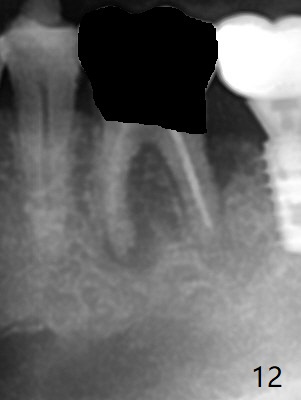

Venopuncture is conducted (Fig.1) for PRF and sticky bone (cortical chip and .5 cc ß-TCP). After use of proximators at #19, cowhorn forceps are applied, resulting in metal crown dislodgement. Since there is distal bone loss, distal socket sheath is contemplated. The tooth is sectioned. When an elevator is inserted between the roots, the distal root is loosened first. The 2 roots are removed, revealing a rounded end septum (Fig.2 S) and a larger distal socket. To avoid osteotomy deviation over the septum, a 12 mm bone trimmer is used, followed by point drill (Fig.3 *). But the lower half of the implant is deviated mesial (Fig.4) with decreased torque (~ 10 Ncm). To overcome this misfortune, the roots should not be removed until osteotomy is finished. Dual zones of bone graft is conducted. Sticky bone is placed until the plateau of the implant with a healing screw in place (Fig.4 * (bone zone)). After placement of a pair abutment, the same bone graft is packed until the margin of the abutment (Fig.5 * (soft tissue zone)). An immediate provisional is fabricated to close the socket with a piece of PRF as well. Fig.6-11 explains why the lower half of the implant deviates to the mesial socket, while Fig.12-16 illustrates how to prevent the deviation. After extraction of #19 (Fig.6,7), the crest of the septum is flattened (Fig.8 arrowhead) to prevent the initial deviation (Fig.9 red line). When a drill reaches a space (a socket, mesial in this case), the drill is deflected to the least resistant area (Fig.10 a bent red line), leading to the implant deviation apically (Fig.11 green). To prevent the apical deviation, therefore, the roots of the affected tooth is temporarily not removed (Fig.12). The osteotomy should not deviates with surgical guide because of similar density between the tooth and the bone (Fig.13). When the osteotomy is finished (Fig.14), the roots are extracted (Fig.15). The implant to be placed should not have deviation (Fig.16 green). The papillae are maintained by the immediate provisional 11 days postop (Fig.17). The incompletely seated abutment at #18 (Fig.5 <) is reseated completely 6 months postop (Fig.18). Crestal bone forms distal to #19 implant. There is no bone loss 4 months and 3 years 1 month post cementation at #19 and 18, respectively (Fig.19,20).